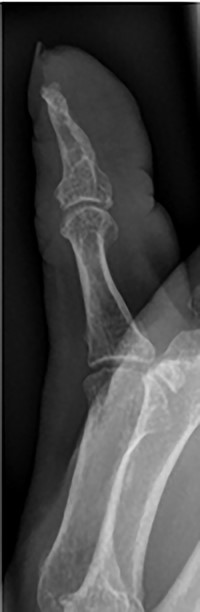

The patient was then reviewed 6 weeks after her initial presentation, following the results of the sarcoma MDT, which confirmed a benign tumour. At this point, the patient reported some tenderness around the surgical incision, but that her symptoms were improving. It was thought that she had no signs of ongoing infection in the thumb. The outcome was for monitoring of her symptoms with no indication for surgical excision. She had a follow-up X-ray in 6 weeks’ time that showed resolution of the lytic lesion (Figs 6 and 7).

AP follow-up radiograph of right thumb 6 weeks post-admission showing resolution of lytic lesion.

Lateral follow-up radiograph of right thumb 6 weeks post-admission showing resolution of lytic lesion.